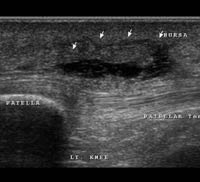

Prepatellar bursitis